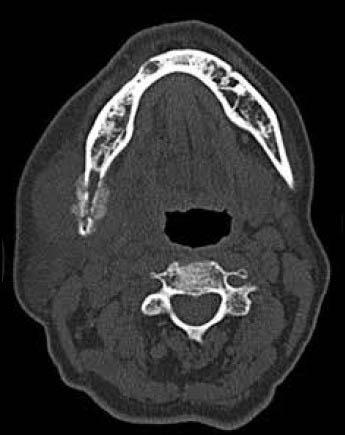

Mandibular metastasis from a pulmonary squamous cell carcinoma.

Metastatic tumors to the jaws and oral tissues are rarely encountered, accounting for less than 1% of all malignant tumors affecting the mouth. Although, metastasis to the mandible from a pulmonary carcinoma is extremely rare, when it does occur it mimics more common pathoses such as odontogenic cysts, osteomyelitis, space infections making its diagnosis even more challenging. Metastasis should be taken into account especially in patients with chronic history of smoking and sudden onset of paresthesia. The rarity of such cases has also resulted in there being no definitive consensus on managing them.

转移至颌骨和口腔组织的肿瘤很少见,占所有口腔恶性肿瘤的比例不到1%。虽然肺癌转移至下颌骨极为罕见,但一旦发生,它会模仿更常见的病症,如牙源性囊肿、骨髓炎、间隙感染,这使得其诊断更具挑战性。特别是对于有长期吸烟史且突然出现感觉异常的患者,应考虑转移的可能性。此类病例的罕见性也导致在治疗方法上没有明确的共识。